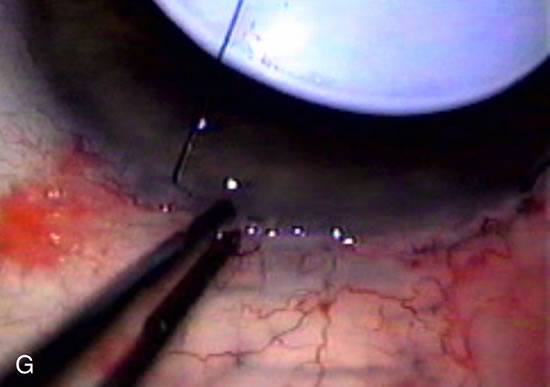

Fig. 8. Bleb appearance after limbus-based versus fornix-based conjunctival flaps. Even though the IOP is thought to be equivalent between limbus and fornix-based conjunctival flaps, the final bleb appearance varies considerably. A. During a limbus-based approach, an incision through conjunctiva 10 mm posterior to limbus will sever through multiple arterial vessels, increasing the likelihood of an avascular bleb. B. The tissues are dissected down to the sclera further cutting feeder vessels from Tenon's capsule. C. The wound is closed inciting a cascade of wound healing events that may ultimately lead to scarring producing a barrier to aqueous flow. D. This leads to walling off of a bleb that has lost some of its overlying vascularity (pale cystic avascular bleb). E. During a fornix-based conjunctival approach, the incision is made at the limbus and tissues undermined. F. The incision is closed at the limbus; no conjunctival vessels are severed over the bleb area. G. This fosters the formation of a shallow diffuse pale bleb with a normal vessel pattern.